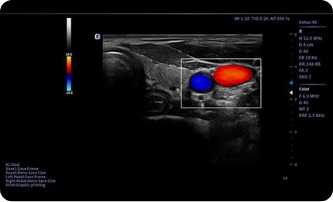

Obrazy kliniczne